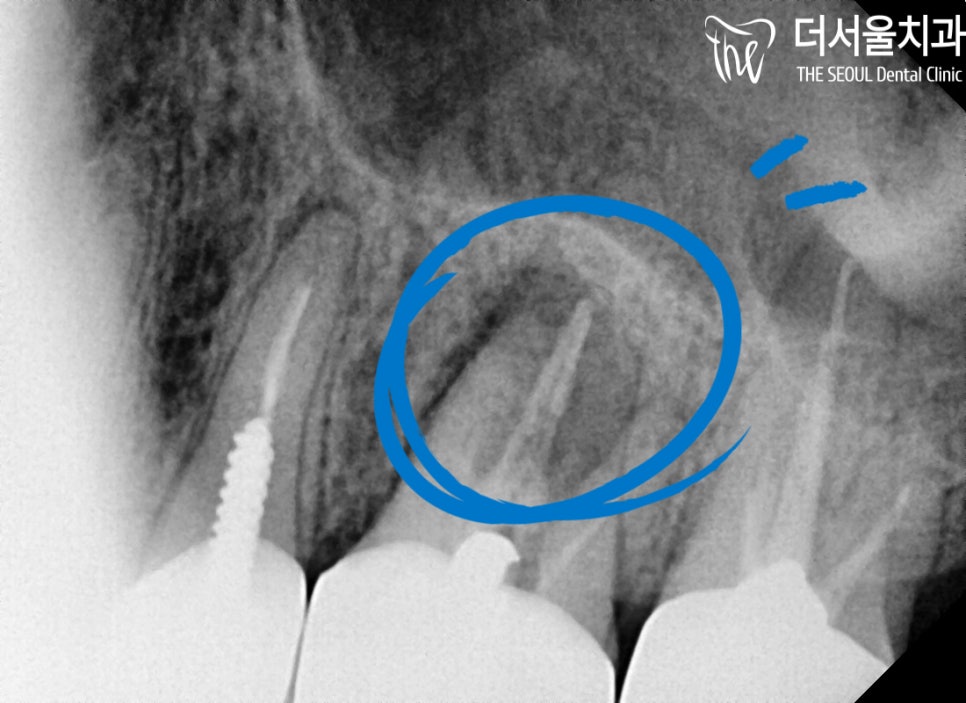

좀 더 정확한 진단을 내릴 수 있도록

X-Ray 촬영을 통하여

이미 잇몸 속은 시커멓게

변해있는 것을 볼 수 있는데요.

어쩔 수 없이 치아 재신경치료를

받으셔야 되는 상황이었습니다.